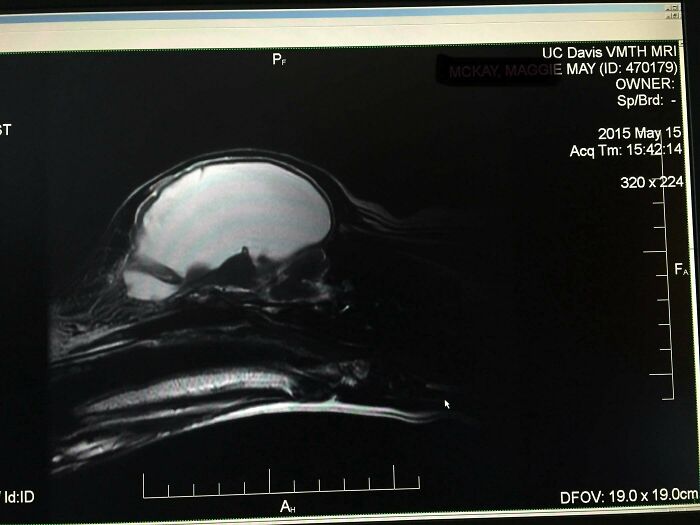

#2 After Having A Dog For 6 Years, We Found Out She Had (Almost) No Brain

We’d had this dog 6 years, she’d had a litter of puppies, and lived a normal life (although we always noticed she was a little off). She had a seizure, so we took her to the vet. They ran labs and noticed her sodium was extremely low and kept her overnight. She was then sent to UC Davis where the vets were surprised she could walk based on her labs. After days of testing they did an MRI and discovered she had hydrocephalus and 95% of her brain cavity was fluid. All of the white you see in the MRI was fluid. Second picture is a comparison to a “normal” dog.

And her low sodium levels were her body’s way of keeping her brain in some form of homeostasis. They sent her home with instructions to provide lots of water and that was it. She lived until 12 when she started having regular seizures and we had to say goodbye.

Our weirdo medical miracle